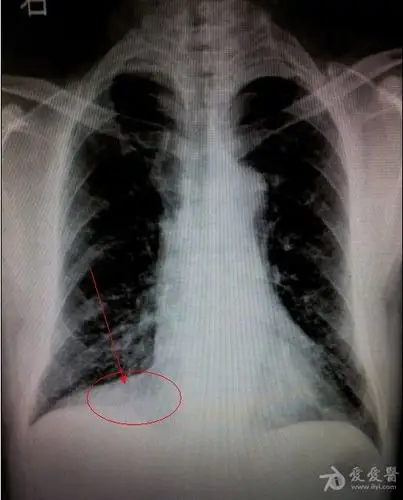

右心膈角是什么